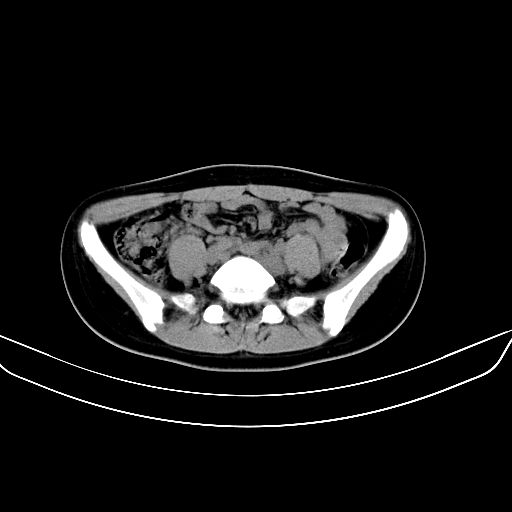

以下是引用zsl6918在2008-7-11 21:40:00的发言:[br]双侧骶髂关节骨质破坏以下三分之一为主,符合强直性脊柱炎表现

以下是引用zhangzhongshou在2008-7-11 21:41:00的发言:[br]患者是女性,hla-b27抗原(—),首先不太考虑强直性脊柱炎,建议查类风湿因子,骶髂关节改变考虑类风湿性关节炎可能性大,建议进一步检查。